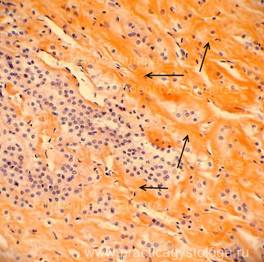

НАДПОЧЕЧНИК (1объект) - в срезах представлены преимущественно значительно утолщенный корковый слой надпочечника в состоянии неравномерного кровенаполнения (участки слабого кровенаполнения граничат с очагами капиллярно-венозного полнокровия). Слабый и слабо-умеренный очаговый отёк стромы. На большей площади срезов представлен распространённый фрагмент светлоклеточной аденомы надпочечника: обилие кучно расположенных крупных клеток по типу адренокортикоцитов, цитоплазма которых переполнена липидными (липоидными включениями, как бы «вспенена» ими). В отдельных полях зрения тонкие соединительнотканные перемычки.

Рис. 6, 7. Светлоклеточная аденома надпочечника. Окраска: гематоксилин и эозин. Увеличение х100 и х250. Цветной и чёрно-белый вариант.